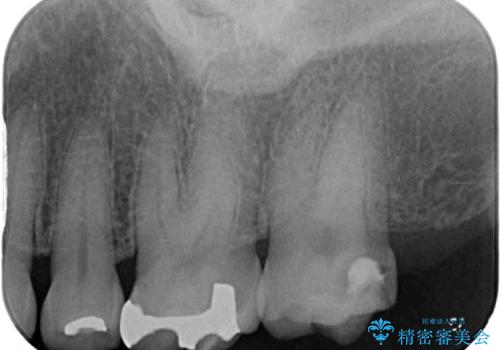

- 奥歯の銀歯がすぐに外れてしまうとのことで来院された患者様です。

何度か銀歯の詰め物を作ったものの、しばらくすると外れてしまうそうで、来院時には銀歯のない状態でした。

咬み合わせをみると、奥歯に負担がかかりやすいことが分かったので、適合がよく、硬さが歯と近いPGAインレー(白金加金合金インレー)にて修復治療を行うこととしました。